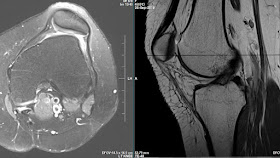

Presented with pain and swelling lt knee. rt knee had a patelelofemoral mpfl reconstruction 10 months ago. no major complaints, although apprehension is positive, post trochleoplasty and MPFL reconstruction pics are below

Trochlear bump ie: ski jump has be removed the trochlear groove lateraised correcting the TT/TG distance , trochleoplasty and mpfl  reconstruction done